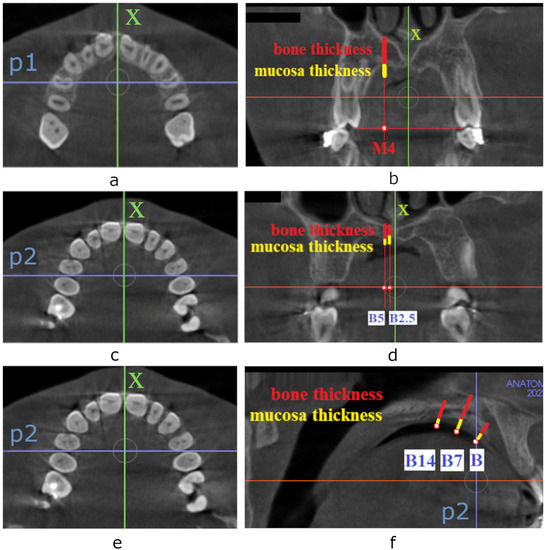

2.2. Measurements

- the horizontal plane passing through the right and left Orbitale and right and left Porion points;

- the frontal plane passing through the right and left Porion point, perpendicular to the horizontal plane; and

- the sagittal plane passing through the Nasion point, perpendicular to the horizontal and frontal planes.